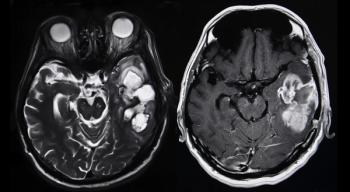

This review focuses on clinical developments and management of newly diagnosed glioblastoma, and includes a discussion about the incorporation of molecular features into the classification of this disease.

In Part 2 of this two-part series, we review the clinical evidence in support of combining immunotherapy with stereotactic radiosurgery for the treatment of brain metastases; examine controversies regarding radiation dose and fractionation, as well as temporal sequencing of multimodality treatment; and discuss future directions in combined therapy.

In this review, we highlight preclinical and clinical data to support the rationale for combination of stereotactic radiosurgery with immunotherapy for the treatment of brain metastases; describe some areas of controversy, especially with regard to radiation fractionation and the timing of combination therapy; and discuss ongoing research into multimodality treatment of CNS tumors.